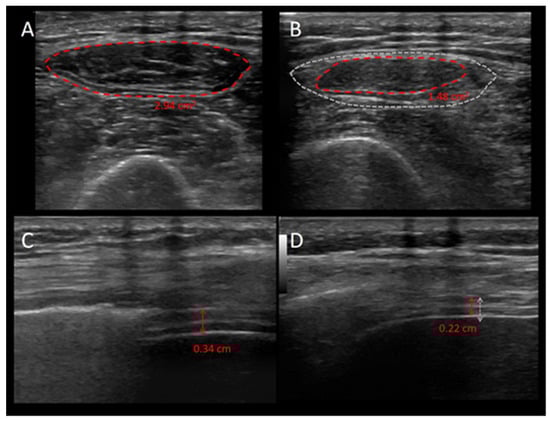

- Formenti, P.; Umbrello, M.; Coppola, S.; Froio, S.; Chiumello, D. Clinical review: Peripheral muscular ultrasound in the ICU. Ann. Intensive Care 2019, 9, 57. [Google Scholar] [CrossRef]

- Puthucheary, Z.A.; Phadke, R.; Rawal, J.; McPhail, M.J.W.; Sidhu, P.S.; Rowlerson, A.; Moxham, J.; Harridge, S.; Hart, N.; Montgomery, H.E. Qualitative Ultrasound in Acute Critical Illness Muscle Wasting. Crit. Care Med. 2015, 43, 1603–1611. [Google Scholar] [CrossRef]

- Umbrello, M.; Guglielmetti, L.; Formenti, P.; Antonucci, E.; Cereghini, S.; Filardo, C.; Montanari, G.; Muttini, S. Qualitative quantitative muscle ultrasound changes in patients with COVID-19-related ARDS. Nutrition 2021, 91–92, 111449. [Google Scholar] [CrossRef] [PubMed]

- Parry, S.M.; El-Ansary, D.; Cartwright, M.S.; Sarwal, A.; Berney, S.; Koopman, R.; Annoni, R.; Puthucheary, Z.; Gordon, I.R.; Morris, P.E.; et al. Ultrasonography in the intensive care setting can be used to detect changes in the quality and quantity of muscle and is related to muscle strength and function. J. Crit. Care. 2015, 30, e9–e14. [Google Scholar] [CrossRef]